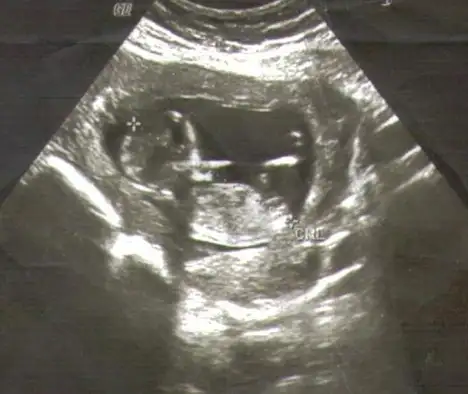

canım bu görüntüsü daha yeni sayılır 13+2 günlükken daha net sanki bakabilirmisin

gördüğüm çıkıntı paralel canım buyuk ihtimal bebişin kız , burda tahmi yapıyoruz elbette yanıladabiliriz umarım gönlündeki sağlıkla olur